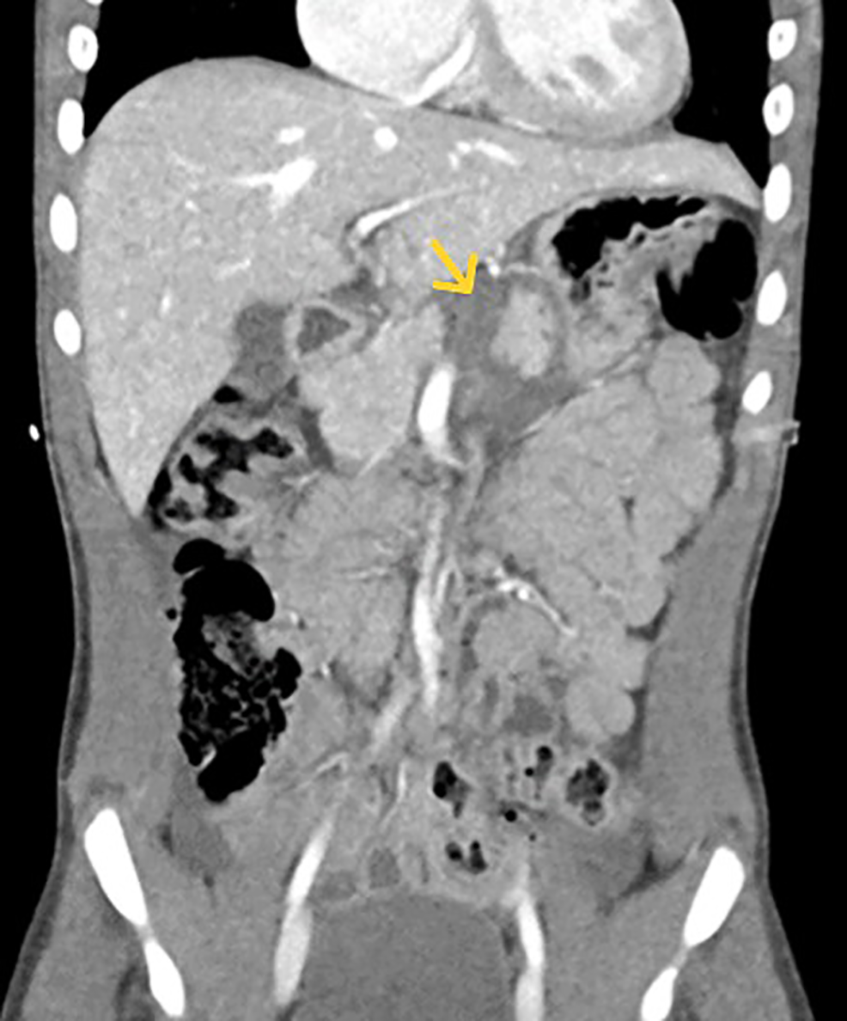

Three EUS procedures with lumen-apposing metal stents (LAMS) were performed to manage acute necrotizing pancreatitis with pseudocyst formation (Figures 4, 5A,B) following EUS-guided drainage of pseudocysts, avoiding the need for surgical interventions. Pancreatic necrosectomy was performed using a standard esophagogastroduodenoscopy (EGD), navigating through the AXIOS™ stent (Boston Scientific, Marlborough, Mass, USA) and using biopsy/rat-tooth forceps for the removal of any necrotic pancreatic tissue. Technical success was achieved in 100% procedure.

Figure 4. Computed tomography (CT) abdomen demonstrating a pancreatic pseudocyst (indicated by the yellow arrow).